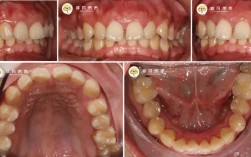

诊疗项目覆盖全年龄段各类牙齿畸形问题,儿童早期矫治针对3-12岁儿童,通过功能性矫治器(如MRC、罗慕)干预地包天、牙齿拥挤等问题,引导颌骨正常发育,降低后期矫正难度;青少年矫治以传统金属托槽、陶瓷托槽为主,结合自锁托槽技术,缩短复诊间隔,提升矫正效率;成人矫治注重美观与功能协调,提供隐形矫正(隐适美、时代天使)、舌侧矫正等隐形化选择,满足职场人士对美观的需求;针对骨性畸形患者,科室联合正颌外科开展术前术后正畸,通过精准的牙齿移动为手术创造条件,实现面部形态与咬合功能的同步改善,还开展牙周病正畸联合治疗、种植体支抗技术等特色项目,为复杂病例提供解决方案。

服务流程上,郑州中心医院正畸科推行“一站式”诊疗模式,患者初诊后,医生会进行全面的口腔检查(包括口内检查、模型制取、X光片拍摄等),结合数字化分析制定初步方案;与患者充分沟通后,确定最终治疗计划并签订知情同意书;治疗过程中,护士全程协助,定期跟踪患者牙齿移动情况,及时调整方案;矫正结束后,提供个性化保持器及长期维护指导,降低复发风险,科室还开设了正畸咨询热线和线上随访平台,为患者提供便捷的术后服务。